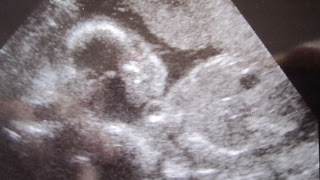

I walked myself up to labor and delivery, even though they offered me a wheelchair. They got all sorts of information from me, and hooked me up to monitors to check on the baby and contractions. They drew blood and took a urine sample, and put tons of bracelets on me. I had been there for a good 30 minutes before they ever even addressed the question of whether or not my membranes had ruptured or not! They did a vaginal exam to find that my cervix was right in the front, as well as the baby's head! I was 2.5cm and 80% effaced, which was the same as it had been 5 days earlier at my last appointment. They pushed up on baby's head, and fluid gushed out, confirming that my membranes had in fact ruptured. My unchanged cervix was apparently sufficient evidence that my body could not produce sufficient contractions on its own and that I needed pitocin. I was INFORMED that I would be put on pitocin because I was now on a timeline. I refused it because I wanted to give my body a chance to kick-start labor on its own before allowing my labor to be augmented artificially.